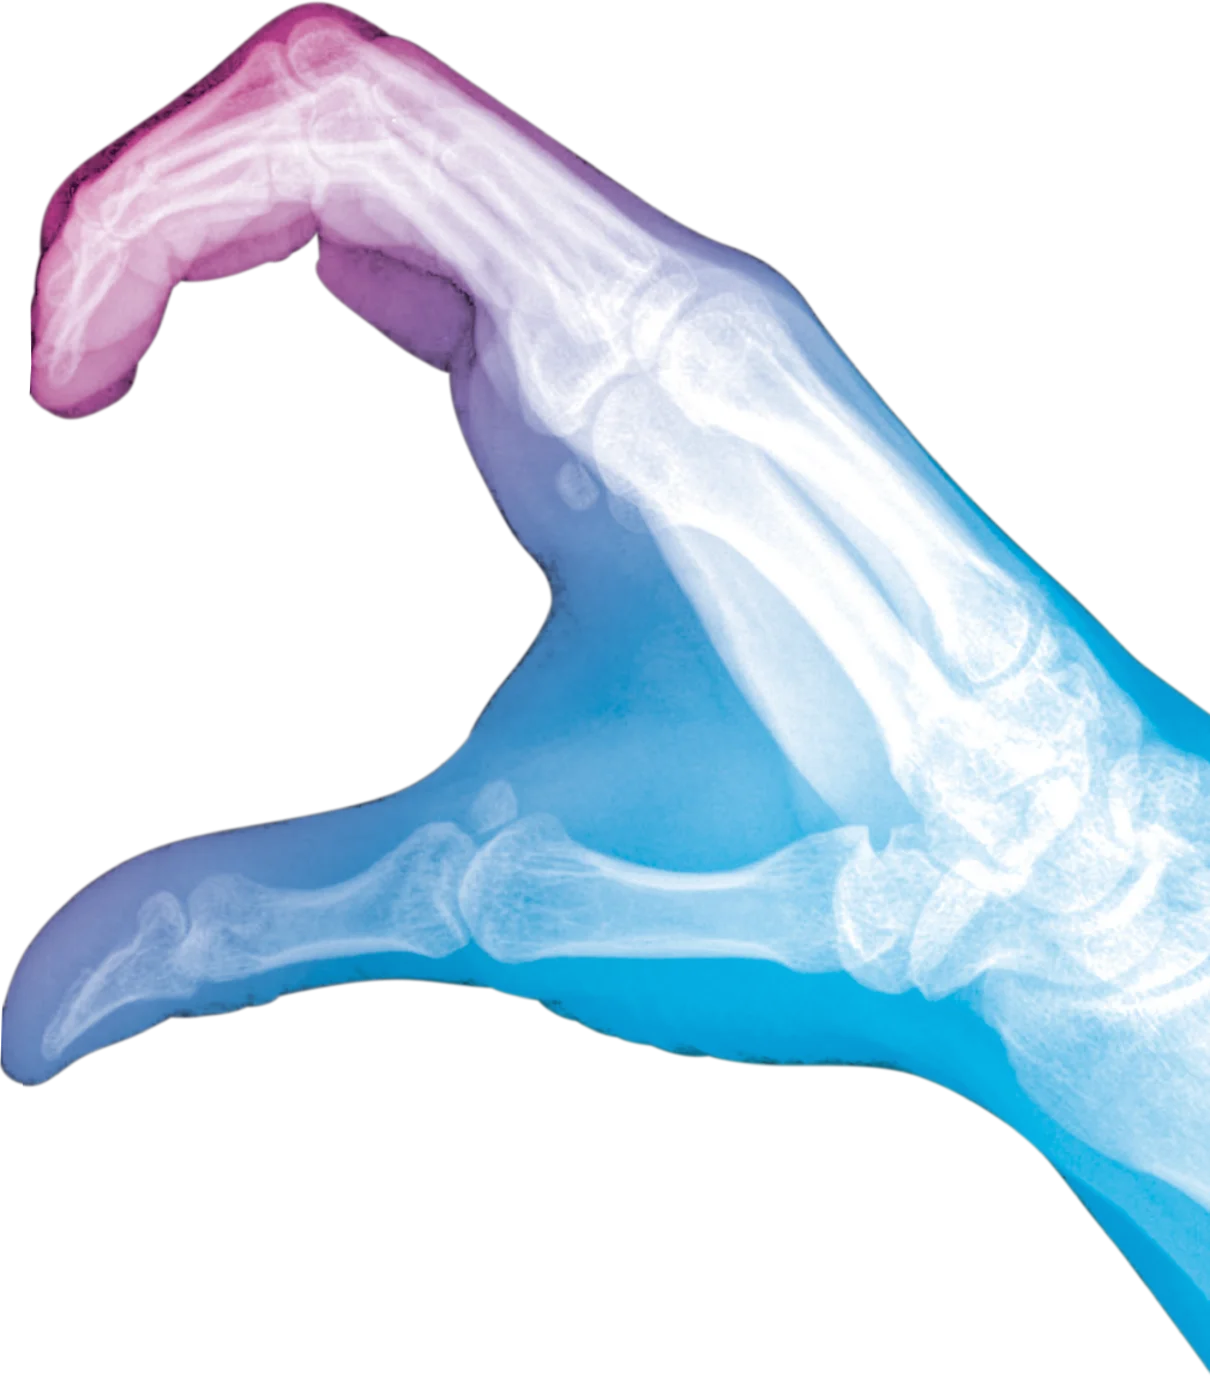

Als Medizinische Technologin bzw. Medizinischer Technologe für Radiologie (MTR) bist du ein unverzichtbarer Teil des medizinischen Teams. Du arbeitest eng mit Ärztinnen und Ärzten zusammen und unterstützt maßgeblich die Diagnostik durch bildgebende Verfahren wie Röntgen, Computertomographie (CT) und Magnetresonanztomographie (MRT). Diese Verfahren liefern wichtige Informationen zur Erkennung und Beurteilung von Krankheiten oder Verletzungen und tragen entscheidend zur Therapieplanung bei.

Als MTR bist Du ein wichtiger Teil des medizinischen Teams, arbeitest eng mit Ärzt:innen zusammen und bist so Teil der Gesundheitsversorgung von Patient:innen. Deine Hauptaufgabe als MTR in der Radiologie besteht darin, Untersuchungen mittels bildgebender Verfahren wie Röntgen, Computertomographie (CT) und Magnetresonanztomographie (MRT) durchzuführen. Diese Verfahren helfen dabei, Krankheiten und Verletzungen zu diagnostizieren oder den Behandlungsverlauf zu überwachen.